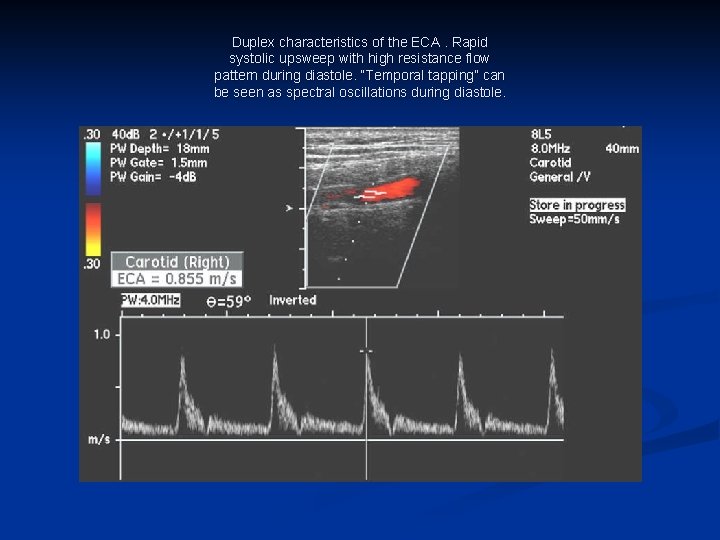

Duplex characteristics of the ECA. Rapid systolic upsweep with high resistance flow pattern during diastole. “Temporal tapping” can be seen as spectral oscillations during diastole.